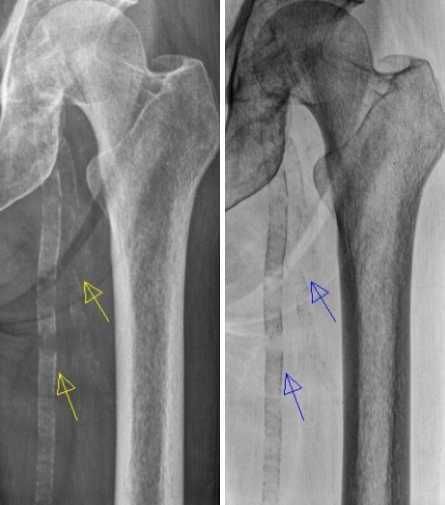

Doctors can diagnose coronary artery calcification using imaging studies. Unfortunately, they may only be able to see the calcification when there is significant calcium buildup in the coronary arteries.

If you have high cholesterol and your doctor suspects coronary artery calcifications, they’ll likely order a computed tomography or CT scan.

A CT scan is a painless imaging test that allows doctors to “score” the amount of calcium present.

More invasive tests for coronary artery calcifications exist. These tests usually involve threading a small, thin catheter through your thigh or forearm to your coronary arteries. Examples include cardiac intravascular ultrasound and intravascular optical coherence tomography.